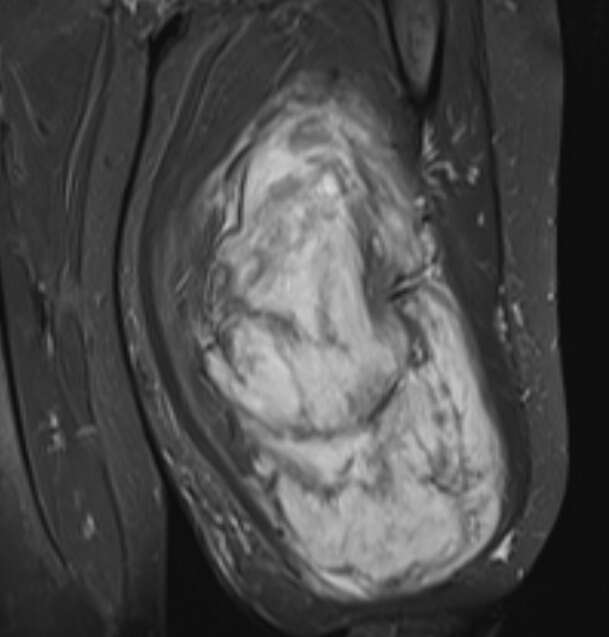

Mardin’de yaşayan 42 yaşındaki H.T., üç yıl önce sağ baldırının arka kısmında fark ettiği yumurta büyüklüğündeki şişliğin giderek büyümesi üzerine Dicle Üniversitesi Tıp Fakültesi Hastanesi’ne başvurdu. Yapılan muayenede yumuşak doku kitlesi olduğu belirlenen şişlik için Ortopedi ve Travmatoloji Anabilim Dalı Öğretim Üyesi Prof. Dr. Emin Özkul ve ekibi ameliyat kararı aldı. Yaklaşık iki saat süren operasyonla çıkarılan kitlenin ağırlığının 5 kilo 668 gram olduğu açıklandı.

Prof. Dr. Emin Özkul, vücutta görülen kitlelerin ihmal edilmemesi gerektiğini vurguladı. Hastanın üç yıl önce başlayan şikâyetlerinin zamanla hızla büyüyen bir kitleye dönüştüğünü belirten Özkul, “Şanslıydı ki sinirlerine zarar vermemişti ve yaşamına fonksiyon kaybı olmadan devam edebilecek. Ancak küçük de olsa yumuşak doku kitleleri mutlaka ciddiye alınmalı ve uzman görüşü alınmalı. Bu hastadan 5 kilo 668 gramlık bir kitle çıkardık, meslek hayatımda gördüğüm en büyüklerden biriydi. Biraz daha büyüse bacağını kurtarmak mümkün olmayabilirdi. Bu nedenle hızlı büyüyen, ağrısız bile olsa şişliklerde vakit kaybetmeden sağlık kuruluşlarına başvurulmalı.” diyerek düşüncelerini aktardı.